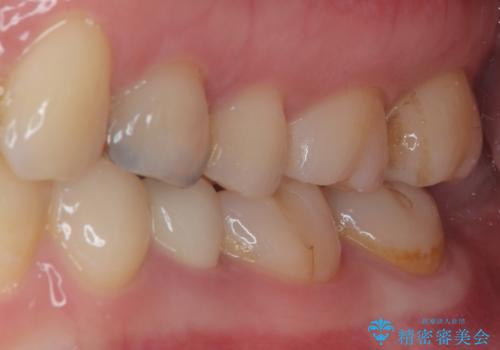

- 左下の被せものが割れたとのことで来院された患者様です。検査の結果、左下の前から4番目の歯はセラミックインレー修復、左下の5番目のところはオールセラミッククラウンによる補綴治療を行っていくことにしました。

拡大鏡視野下で被せもの、虫歯の除去を行い、オールセラミッククラウン、セラミックインレーに適した形に整えました。

適合の良い被せものが入り、審美面も気に入っていただけました。被せものが割れていたという経緯もあったため少しだけ被せものの厚みを多めに確保してあります。